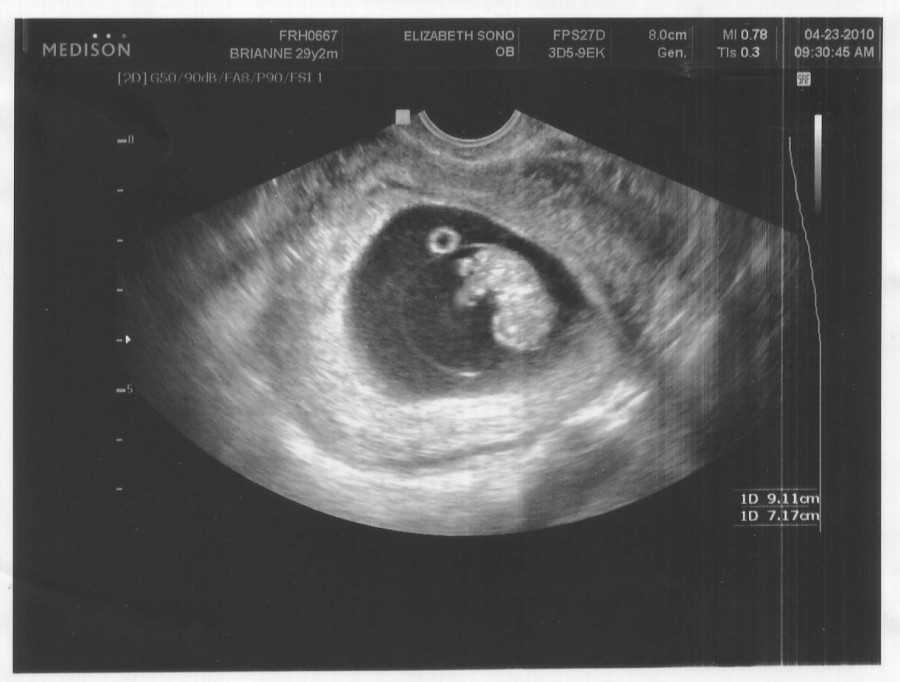

Также показано ультразвуковое исследование плода. Процедура УЗИ позволяет определить срок беременности, толщину плаценты, а также общее состояние яичников и пуповины.

На УЗИ плода на 9 неделе определяется толщина плаценты и общее состояние пуповины. При помощи допплера, будущая мама может отметить частоту сердечных сокращений малыша. Хотя многие внутренние органы уже достаточно развиты, это не всегда можно увидеть на УЗИ на 9 неделе.

Внутренние органы крохи еще могут выступать в виде пупочной грыжи, но нет повода для беспокойства, ведь это совершенно нормальное явление.

На УЗИ на данном сроке обязательным является общая оценка состояния яичников.

УЗИ на сроке 9 недель